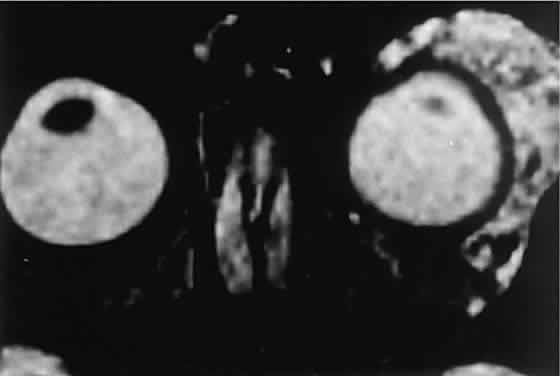

Orbital myositis may represent a greater proportion of cases of IIPT in childhood than in adulthood, and involvement of multiple extraocular muscles may occur more frequently in children than inadults. In orbital myositis, early diplopia and increased discomfort with attempted eye movement are typical symptoms. CT may show enlargement of one or more extraocular muscles in one or both orbits (Figs. 21 and 22). When a single muscle is involved, the specter of a primary or metastatic neoplasm within the muscle may be raised. However, external inflammatory signs, considerable pain and limited motility, and an explosive onset of symptoms within 24 hours all suggest orbital myositis. The uniform enlargement of the muscle, including its tendinous insertion (see Fig. 22), also helps distinguish the process from a neoplasm, which might be expected to produce a more focal, globular expansion. Echography may support the diagnosis of inflammation by showing edema in the episcleral space as a relative sonolucency between the scleral and orbital fat echoes (Fig. 23). Its CT counterpart is an increase in the radiodensity and thickness of the ocular tunica.

Fig. 21. A. This 16-year-old boy had acute onset of bilateral proptosis, pain, diplopia, chemosis, and conjunctival injection. B. Bilateral enlargement of the superior and medial rectus and inferior oblique muscles. Other sections showed similar involvement of other extraocular muscles.

Fig. 22. The uniform enlargement of the left medial rectus muscle, including its tendinous insertion, is characteristic of orbital myositis.

Fig. 23. Acoustic discontinuity between the globe and the orbital fat indicates inflammatory edema in Tenon's space.